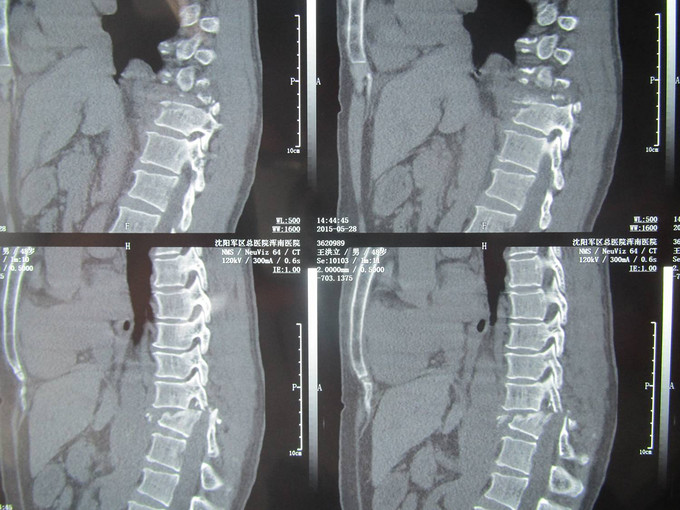

患者及家属述患者于2015-5-28日下午1点,自行驾驶机动车不慎坠入沟中,导致胸腰部疼痛活动受限,无法站立行走。家人急送到沈阳军区总院浑南院区,行CT检查示:胸11椎体压缩骨折;右侧胸11、12腰1横突骨折;胸10、11棘突骨折;右侧肋骨多发骨折;未行任何处理。现患者及家属为求进一步治疗来我院,我科以“胸椎骨折”为主要诊断收入院。患者自受伤以来,无发热,稍感呼吸困难,饮食睡眠正常,二便正常。

入院后完善检查,查无手术禁忌症后行胸11椎体骨折切开复位椎板减压椎弓根钉内固定术